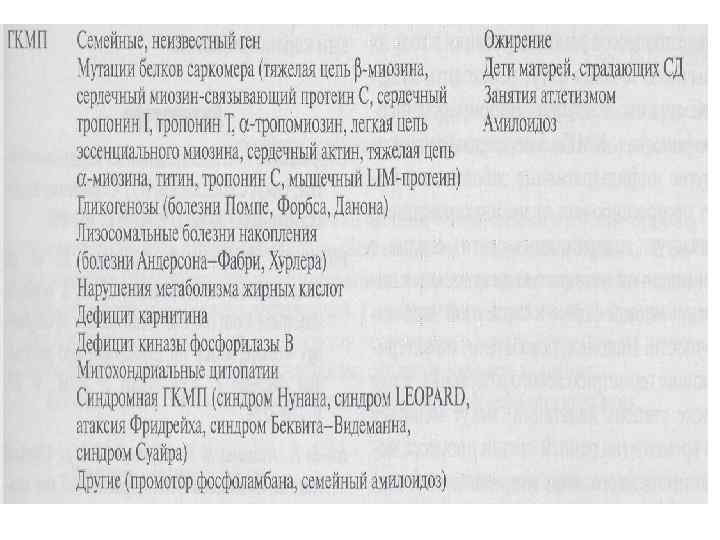

Этиология При ГКМП точечные мутации нарушают взаимодействие протеинов саркомера и Са, что приводит к неэффективному сокращению и развитию гипертрофии • Ген тяжелой цепи кардиального бета-миозина (14 q 11 -12) -35% • Ген тропонина Т (lg 3) -15% • Ген тропонина I (19 р13) • Ген альфа-тропомиозина(15 q 2)- 3% • Ген миозин-связывающего протеина С(11 p 11)15% • Гены легкой цепи миозина (3 p 21 12 q 23) – 1% • Ген актина (15 q 11 -14) • Неидентифицированная мутация в локусе 7 q 3 (сочетание ГКМП с синдромом предвозбуждения желудочков)

Этиология При ГКМП точечные мутации нарушают взаимодействие протеинов саркомера и Са, что приводит к неэффективному сокращению и развитию гипертрофии • Ген тяжелой цепи кардиального бета-миозина (14 q 11 -12) -35% • Ген тропонина Т (lg 3) -15% • Ген тропонина I (19 р13) • Ген альфа-тропомиозина(15 q 2)- 3% • Ген миозин-связывающего протеина С(11 p 11)15% • Гены легкой цепи миозина (3 p 21 12 q 23) – 1% • Ген актина (15 q 11 -14) • Неидентифицированная мутация в локусе 7 q 3 (сочетание ГКМП с синдромом предвозбуждения желудочков)